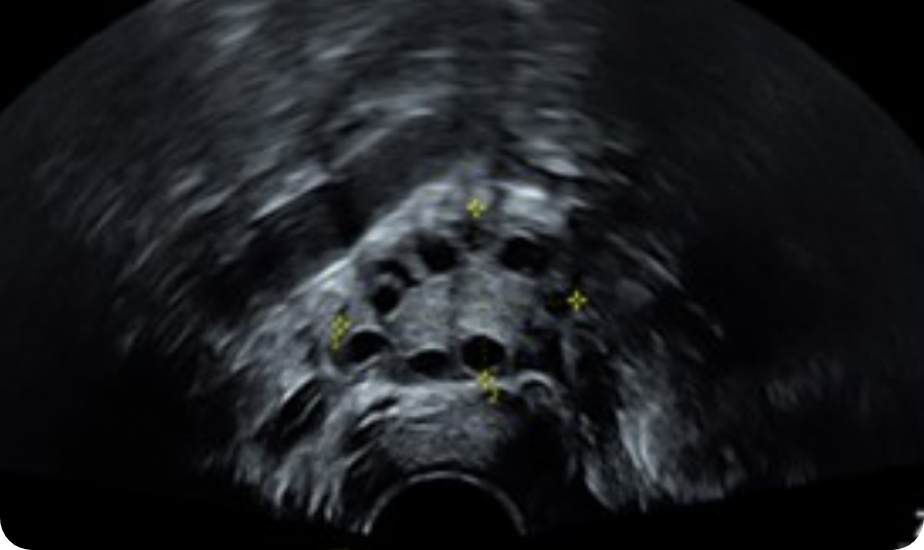

陰道超聲波檢查(TVS)

透過陰道超波檢查,可以評估子宮、卵巢構造是否有先天性異常,並觀察卵巢濾泡的發育情形、子宮內膜厚度與變化。另外,亦能夠篩檢出潛在的子宮肌瘤及子宮內膜異位等常見婦科問題。

透過陰道超聲波檢查,可評估子宮、卵巢構造是否有先天性異常,並觀察卵巢濾泡的發育情形、子宮內膜厚度與變化。另外,也能檢查出潛在的子宮肌瘤及子宮內膜異位等常見婦科問題。輸卵管健康是影響自然懷孕與人工受孕成功的重要關鍵之一。如果輸卵管出現阻塞、沾黏或水腫等問題,會降低自然懷孕機率,亦可能影響人工受孕的成效,甚至降低試管嬰兒的成功率。